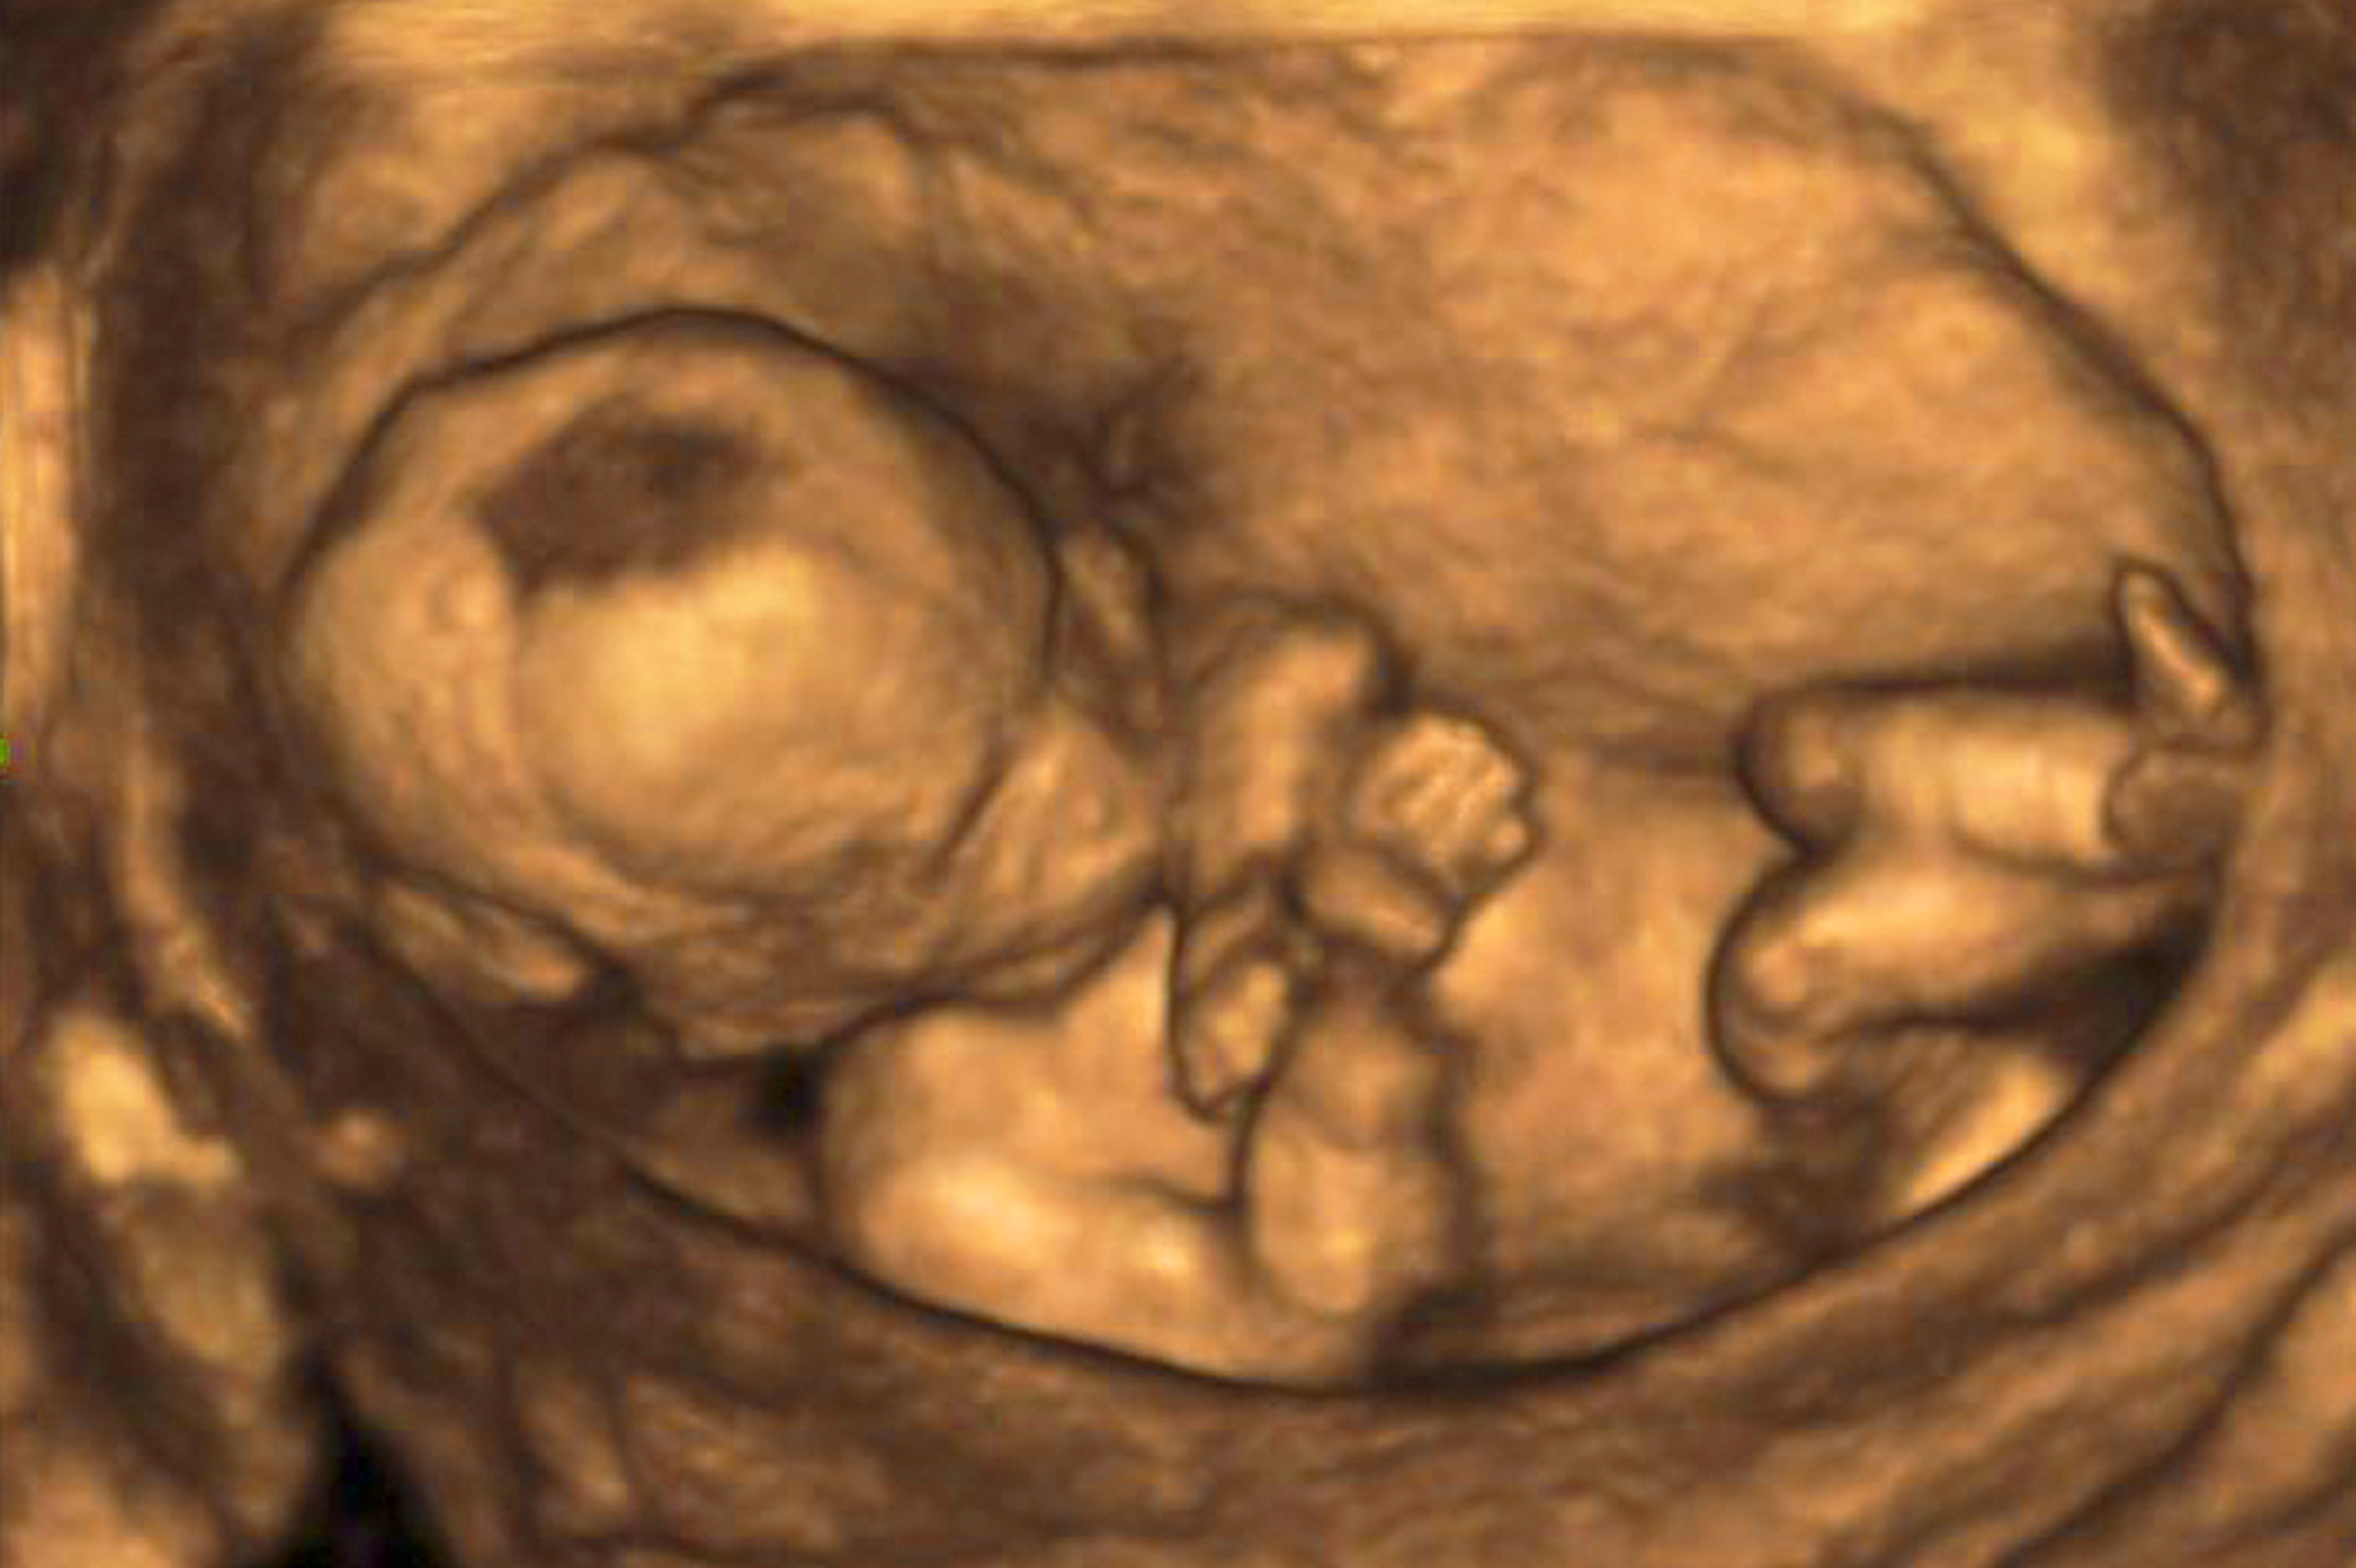

(Vienna, 28 January 2021) The internationally renowned TRUFFLE 2 study (trial of randomized umbilical and fetal flow in Europe) has kicked off at the Medical University of Vienna's Division of Obstetrics and Feto-Maternal Medicine. The aim of the study is to define the best management of fetuses with late onset fetal growth restriction. The study will be coordinated by Christoph Lees from Imperial College London and conducted at 60 centres throughout Europe. Julia Binder will lead the study at MedUni Vienna.

"Late onset fetal growth restriction is a major risk factor for intrauterine death, neonatal morbidity and poor long-term neurological outcomes for the affected children," explains Julia Binder, head of the outpatient clinic for fetal medicine at the Division of Obstetrics and fetomaternal Medicine at the Medical University of Vienna. Currently, there are no clear study results to indicate the preferred mode of management for late onset growth restricted fetuses – watch-and-wait management with close ultrasound monitoring or premature delivery. However, this is a decision with far-reaching consequences, since unsatisfactory early delivery or late delivery can seriously impact the long-term health of these children.

The randomised controlled TRUFFLE 2 study should now provide greater clarity. An interdisciplinary team of obstetricians (Julia Binder, Petra Pateisky, Kinga Chalubinski and Pilar Palmrich) and neonatologists (Kathrin Klebermass-Schrehof, Angelika Berger) from the Comprehensive Center for Pediatrics (CCP) is responsible for the care and treatment of these children before and after birth and hopes that this study will bring new insights and strategies that will improve the management of these children.